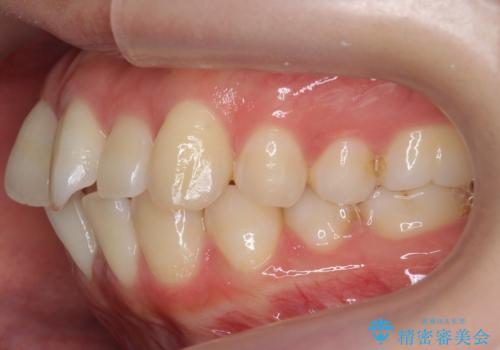

インビザライン モニター治療 前歯のねじれをまっすぐに

- 前歯のねじれを主訴に来院。

インビザラインの部分矯正コースではなく全体矯正コースをご希望でした。

前歯のねじれやがたつきだったため、モニター治療での低価格でのご提案が可能でした。

年齢が10代なこともあり、歯の動きは非常によく、リファインメントなしできれいに並びました。

下の前歯を少し削合して並べています。